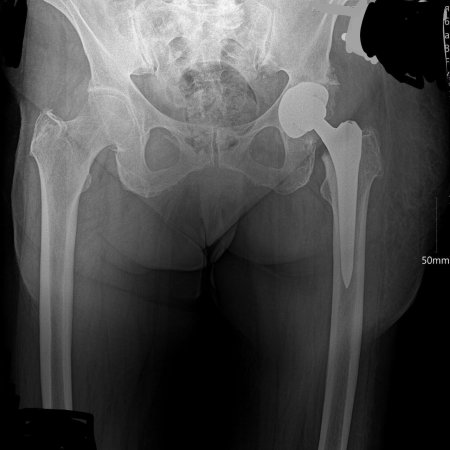

Рентгеновский эффект создает фантастические композиции в этих фотографиях девушки, чье тело становится прозрачным, демонстрируя скелет и внутренние органы. Она позирует в разных позах, ее силуэт светится загадочным свечением. Каждый кадр передает атмосферу научной фантастики и медицинского искусства. Ее кожа кажется полупрозрачной, позволяя увидеть кости и мышцы. Фотографии рассказывают о хрупкости человеческого тела и его внутренней красоте. Девушка то стоит в задумчивости, то делает грациозное движение. Эти иллюстрации вдохновляют на размышления о человеческой анатомии и уязвимости. Каждая картинка - это момент прозрения, когда внешнее уступает место внутреннему. Девушка воплощает образ современной Медузы, сочетающей красоту и загадочность.